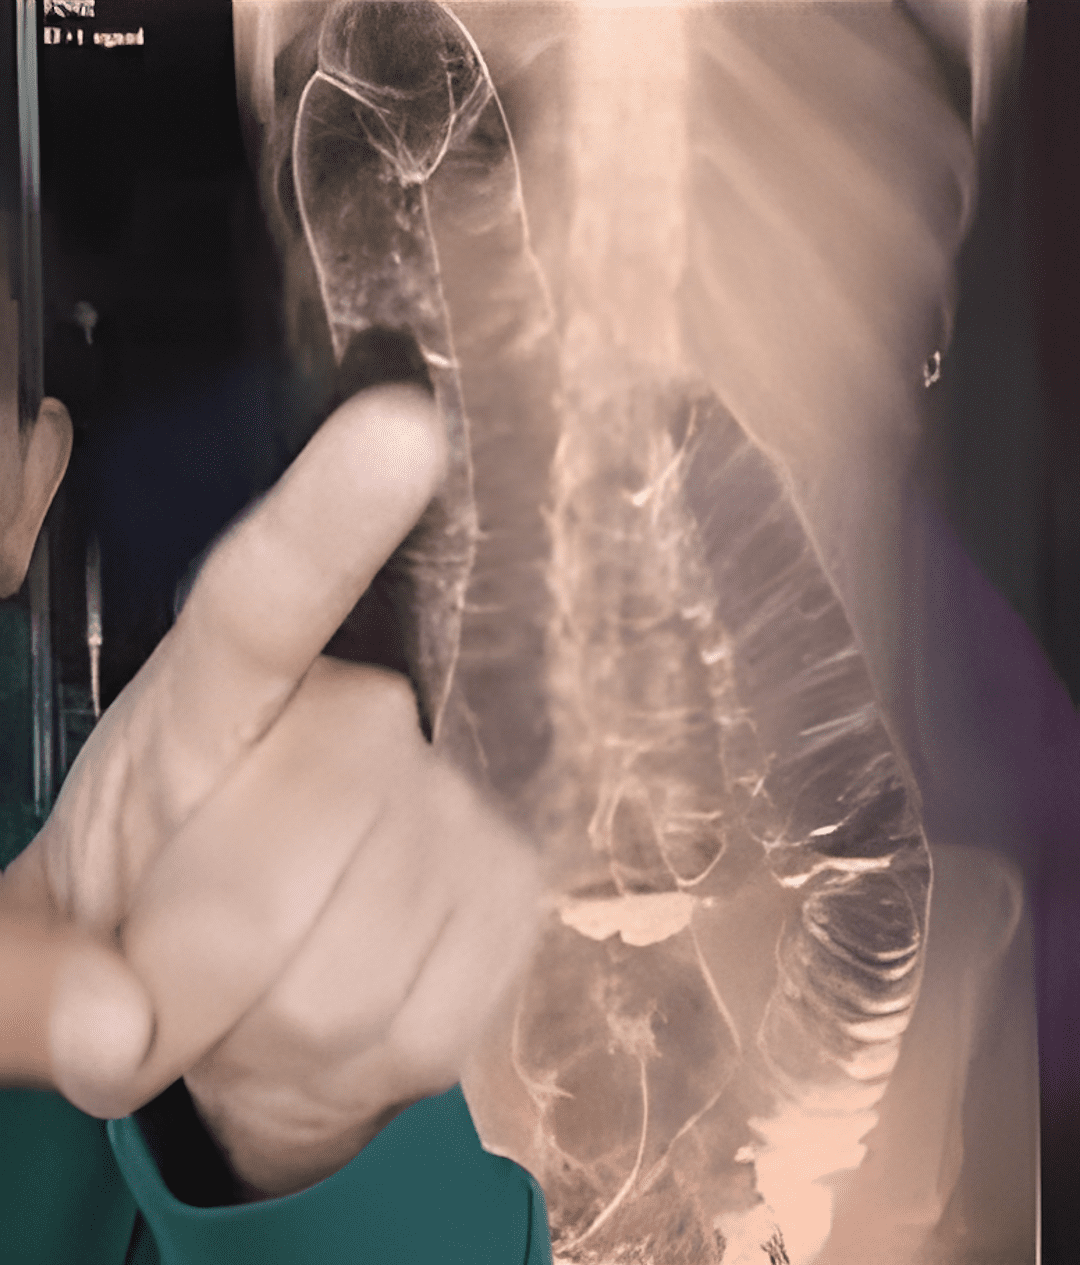

Wie heeft er nou geen last van constipatie? Dit probleem, vaak als onbelangrijk beschouwd, kan een ware nachtmerrie worden als het chronisch wordt. Stel je voor dat je meer dan twee weken geen stoelgang hebt gehad… Dit is precies wat een jonge vrouw overkwam bij wie de overbelaste dikke darm gevaarlijk verwijdde. Een extreem geval, maar een dat de onvermoede gevaren van langdurige constipatie perfect illustreert. Dus, hoe kunnen we voorkomen dat deze spijsverteringsstoornis een dramatische wending neemt?

Als je geen regelmatige stoelgang hebt, hoopt het afval zich op in de dikke darm. Het resultaat: overmatige druk die pijn, een opgeblazen gevoel en, in ernstige gevallen, ernstige complicaties kan veroorzaken .

- Uitzetting van de dikke darm : Na verloop van tijd verliest de dikke darm zijn elasticiteit en wordt het steeds moeilijker om ontlasting te verwijderen.

- Darmobstructie : In extreme gevallen kan de darm door ontlasting volledig geblokkeerd raken, waardoor een spoedoperatie noodzakelijk is .